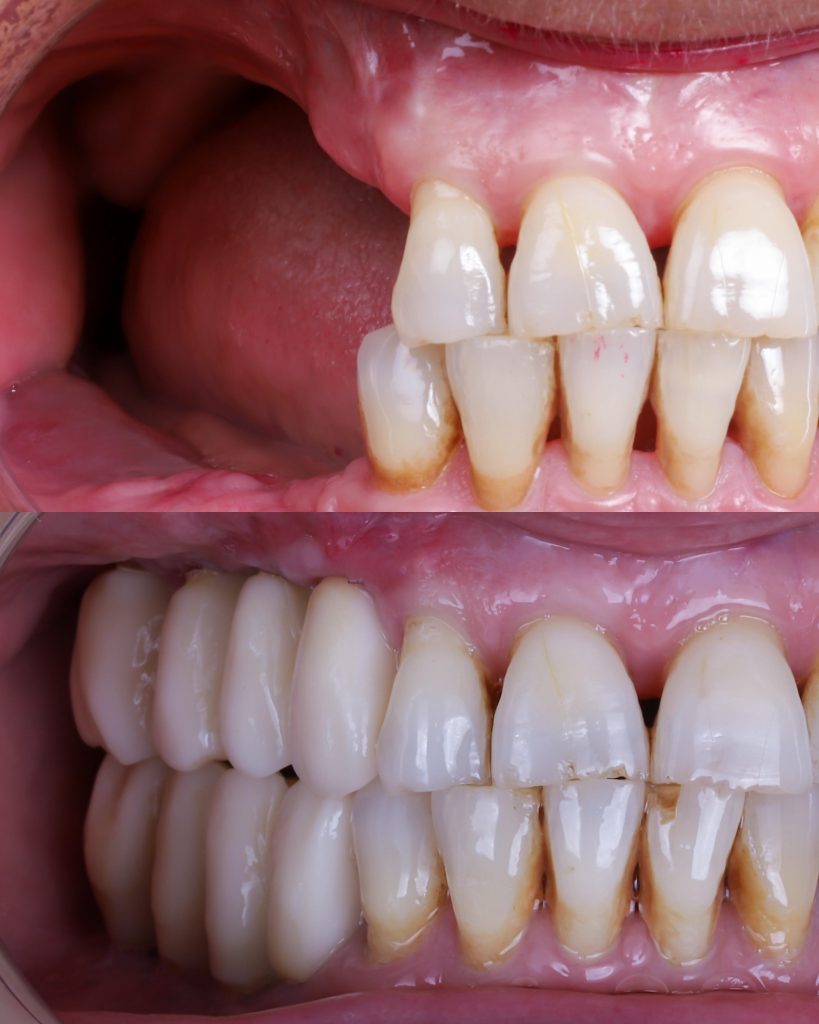

El injerto de hueso dental aporta múltiples beneficios tanto funcionales como estéticos. Las ventajas principales incluyen:

• Permite colocar implantes dentales donde antes no era posible. Es el tratamiento que hace viable la implantología en pacientes con poco hueso.

• Recupera el volumen óseo perdido, mejorando la estabilidad de la futura rehabilitación y garantizando resultados duraderos.

• Mejora la anatomía facial, especialmente en pacientes con mucha reabsorción ósea, devolviendo soporte a labios y mejillas.

• Aumenta la predictibilidad del tratamiento, ya que proporciona una base sólida sobre la que planificar implantes con máxima precisión digital.

• Optimiza la estética final, permitiendo una posición ideal de los implantes para conseguir un resultado más natural.